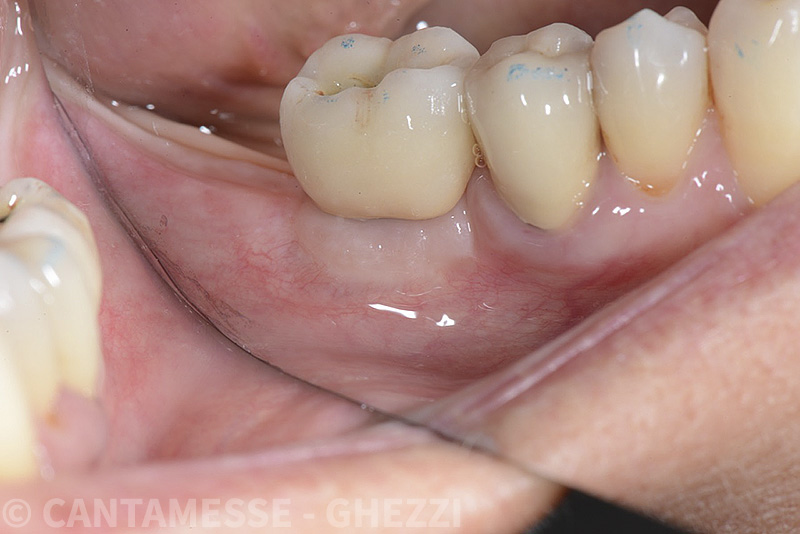

PREMESSA: in seguito all’estrazione dell’incisivo laterale superiore di destra, resasi necessaria per cause batteriche, si decide di affrontare il caso con il posizionamento di un impianto in sostituzione dell’elemento mancante dopo guarigione del sito infetto. Con tecniche rigenerative sia dei tessuti ossei mancanti a causa dell’infezione pregressa, sia dei tessuti gengivali che appaiono inizialmente troppo spostati in alto, si ripristina una corretta morfologia delle parabole (contorni) gengivali e delle papille interdentali (triangoli di gengiva tra due denti vicini).

Vengono utilizzati 2 tipi di provvisori: il primo, cementato ai denti vicini, viene utilizzato dal momento dell’estrazione del dente fino ad impianto osteointegrato (circa 6 mesi); il secondo, avvitato direttamente all’impianto, ha una funzione di prova estetica ma soprattutto di guida per la maturazione dei tessuti gengivali peri-implantari portandoli verso la maturazione completa prima di posizionare la corona finale in disilicato di litio.